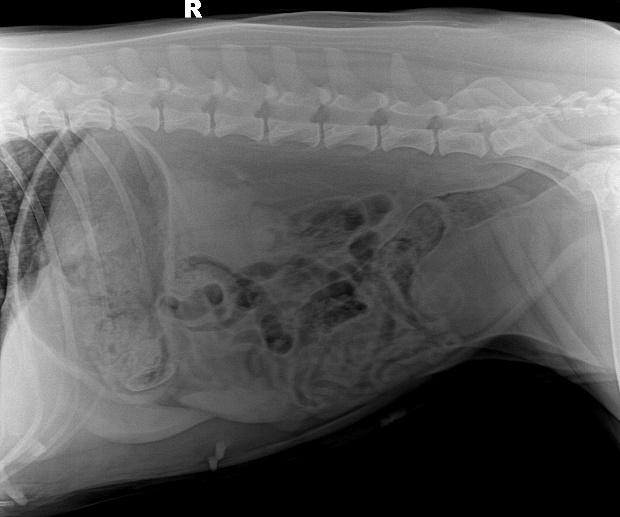

c.X线检查。对于阻线性较强的物质(如金属、骨头)较容易辨别,对于阻线性与组织密度相似的物体较难确定,但是可以通过消化道灌服造影剂判断是否有阻塞或可包裹物体。

机械性肠梗阻的读片要点:1.体积增大;2.形态轮廓变化;3.影像密度变化;4.浆膜细节变化。

犬猫呕吐的鉴别诊断,犬猫呕吐的诊断和治疗

金毛 线性异物